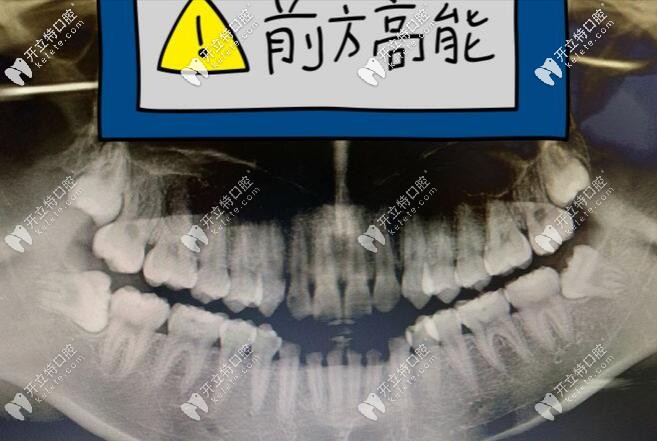

拔牙時候的感受如下圖:

一個醫(yī)生+兩個助理圍著我,就有一種莫名的緊張感;過程就不詳述了,總之就是撬啊,還有掰啊,有一種拔樹的感覺,但是自己沒啥感覺。